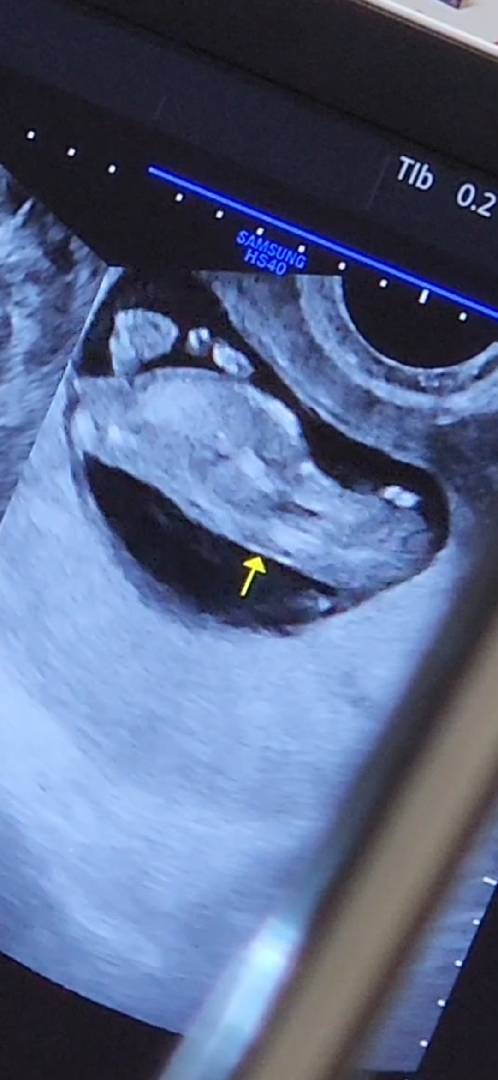

이사진으로 각도법알수있을까요????